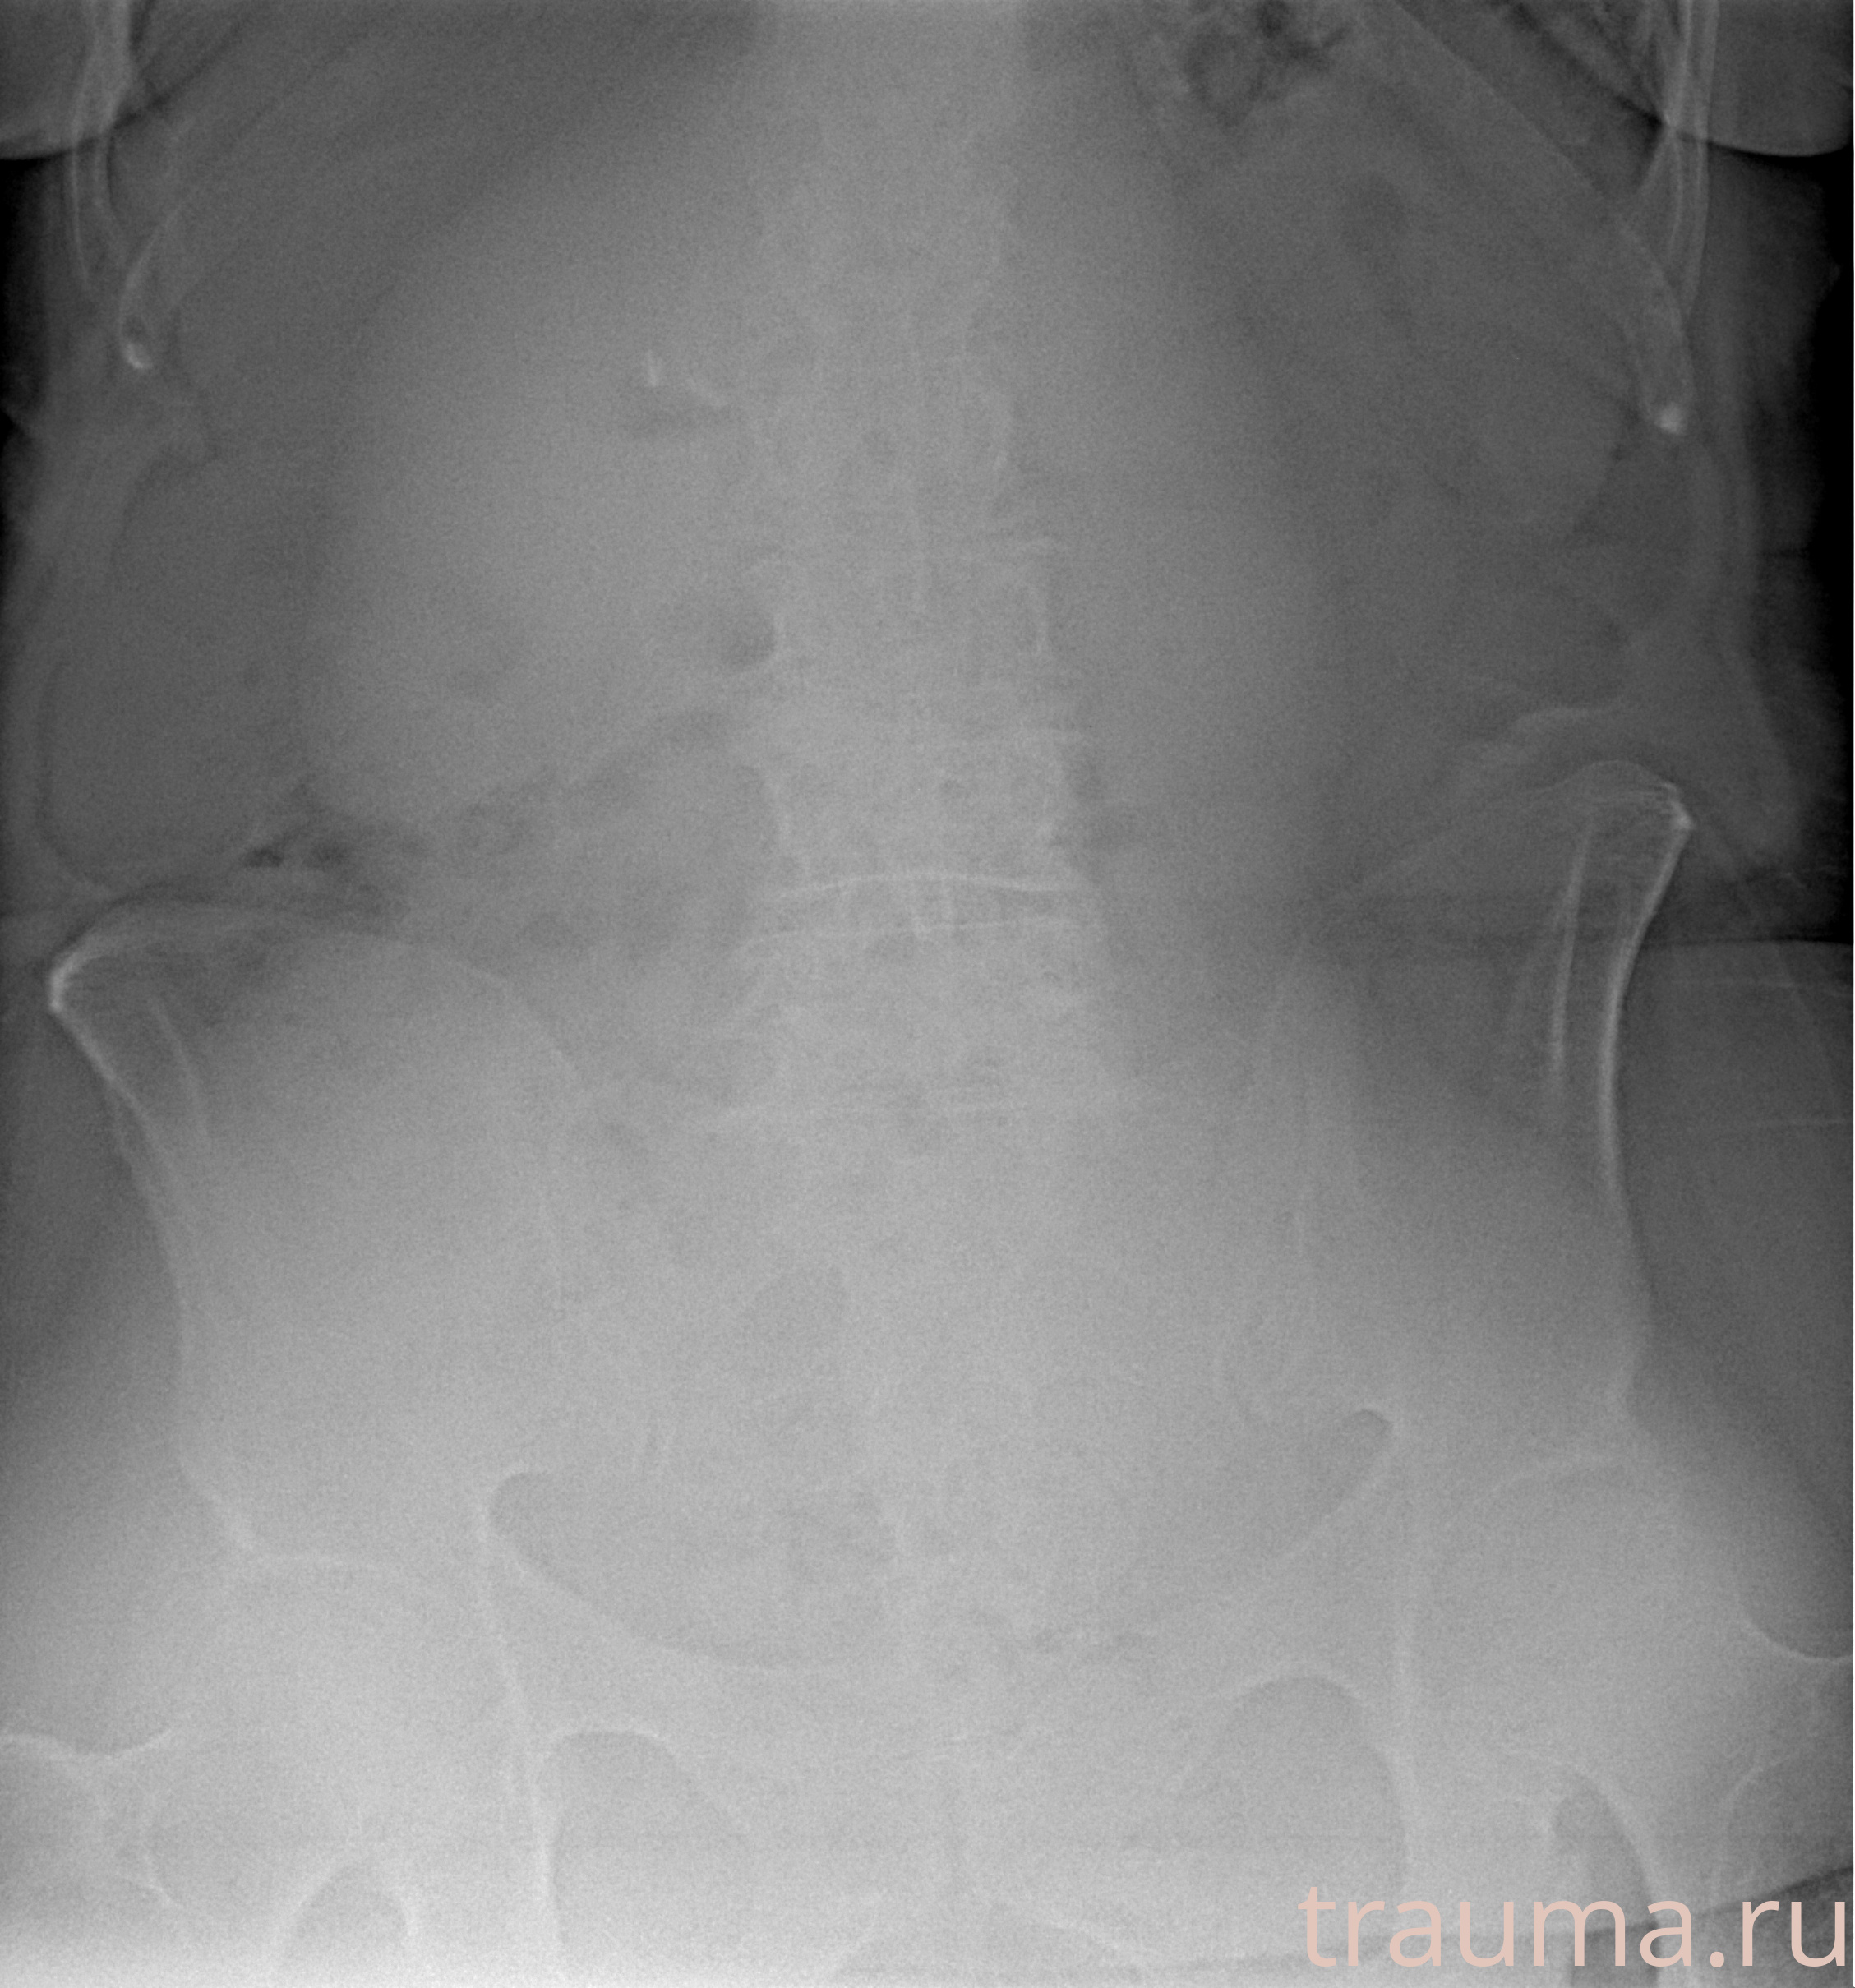

Рентгенограммы

Левая

Рентген на дому: по вашему адресу приезжает врач-рентгенолог, травматолог-ортопед с мобильным рентгеновским аппаратом, проводит диагностику травмы или заболевания, делает необходимые рентгенограммы, дает рекомендации по дальнейшему лечению. Получить качественные снимки в домашних условиях возможно благодаря уникальной методике, разработанной МосРентген Центром для института  Склифосовского